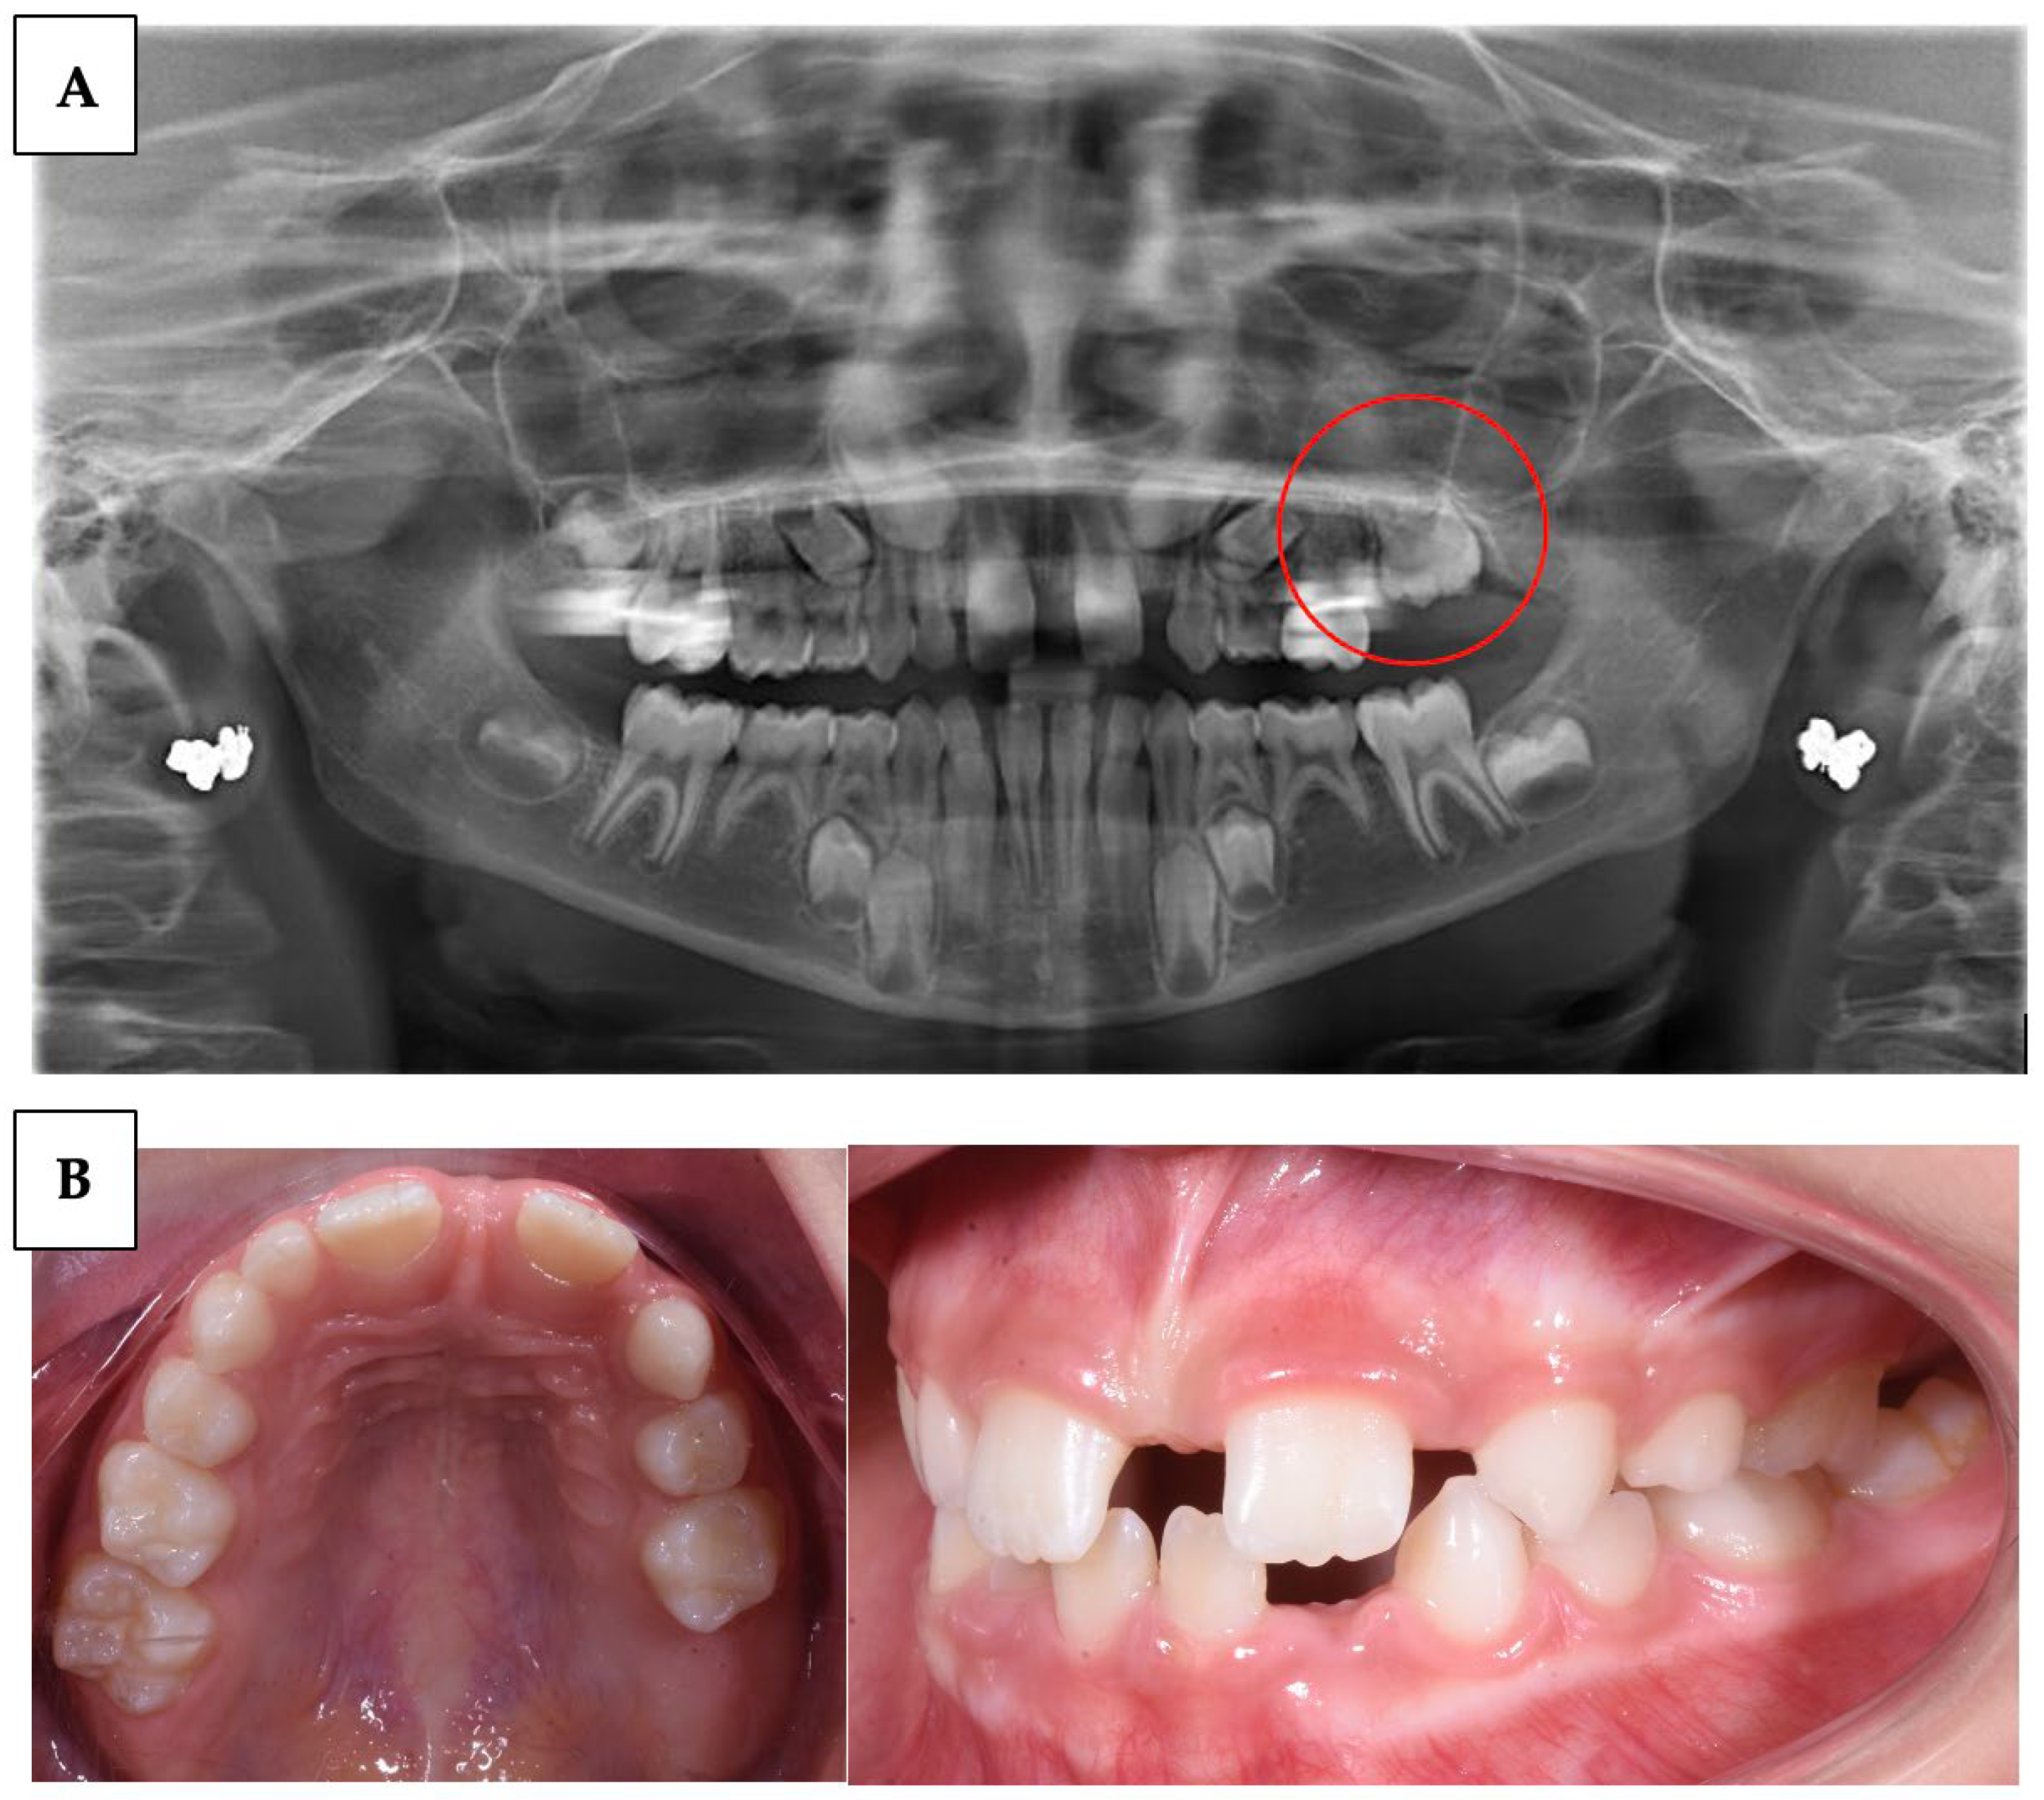

| Grippaudo C. et al. (2018) [10] | RCT | 51 | To investigate the possibility that both primary and permanent teeth may be affected by mutations in the parathyroid hormone 1 receptor (PTH1R). | A study of 29 individuals with infraoccluded teeth involved saliva samples, DNA retrieval, and sequencing of PTH1R gene coding regions. Mutations were examined for genetic information. | The PTH1R gene contains novel mutations affecting primary molars affected by PFE, paving the way for early genetic diagnostics and appropriate care. |

| Wagner et al. (2023) [59] | Case series | 3 | Describe the variability of clinical presentations of PFE associated with pathogenic variants of PTHR1 | Clinical examination, radiological examination, and molecular DNA testing | Multidisciplinary complex treatment, from child to adulthood. |